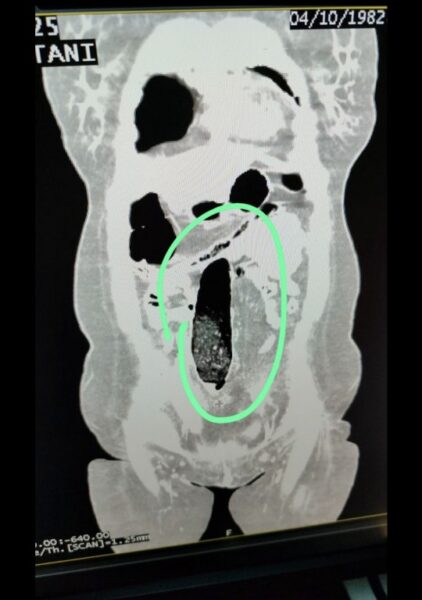

Muş İl Emniyet Müdürlüğü ekiplerince şehirler arası otobüste yakalanan 2 İran uyruklu şahsın vücutlarında uyuşturucu madde ele geçirildi. Muş İl Emniyet Müdürlüğü Narkotik Suçlarla Mücadele Şube Müdürlüğü ekiplerince, il genelinde uyuşturucu madde ticareti ve kullanımının önlenmesine yönelik yürütülen teknik ve analiz çalışmaları kapsamında, şehirler arası otobüslerle uyuşturucu sevkiyatı yapılacağı değerlendirildi. Bu değerlendirme üzerine durdurulan şehirler arası yolcu otobüsünde bulunan 2 İran uyruklu şahıs üzerinde yapılan kontrollerde şüpheli durum tespit edildi. Şahısların iç beden muayeneleri sonucunda, vücutlarının doğal boşluklarında ve bağırsaklarında uyuşturucu madde bulunduğu belirlendi. Tıbbi müdahale sonucu; F.V. isimli kadın şahıstan 3 parça halinde toplam 397,78 gram metamfetamin, S.İ. isimli erkek şahıstan ise 24 adet sentetik hap ile 3 parça halinde toplam 167,68 gram metamfetamin ele geçirildi. Şüpheliler hakkında TCK 188 Uyuşturucu veya Uyarıcı Madde İmal ve Ticareti suçu kapsamında adli işlem yapıldı. Adli mercilere sevk edilen şahıslar tutuklanarak cezaevine gönderildi./İHA